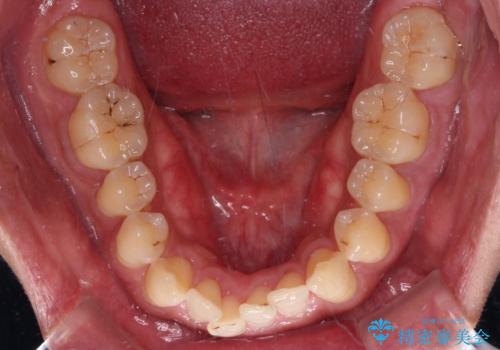

- 前歯のデコボコを気にして来院された患者様です。

インビザラインによるマウスピース矯正も適用となる歯列でしたが、できる限り自己管理の煩わしさのない状態で治したいとのことで、ワイヤー装置にて矯正治療を行うこととしました。